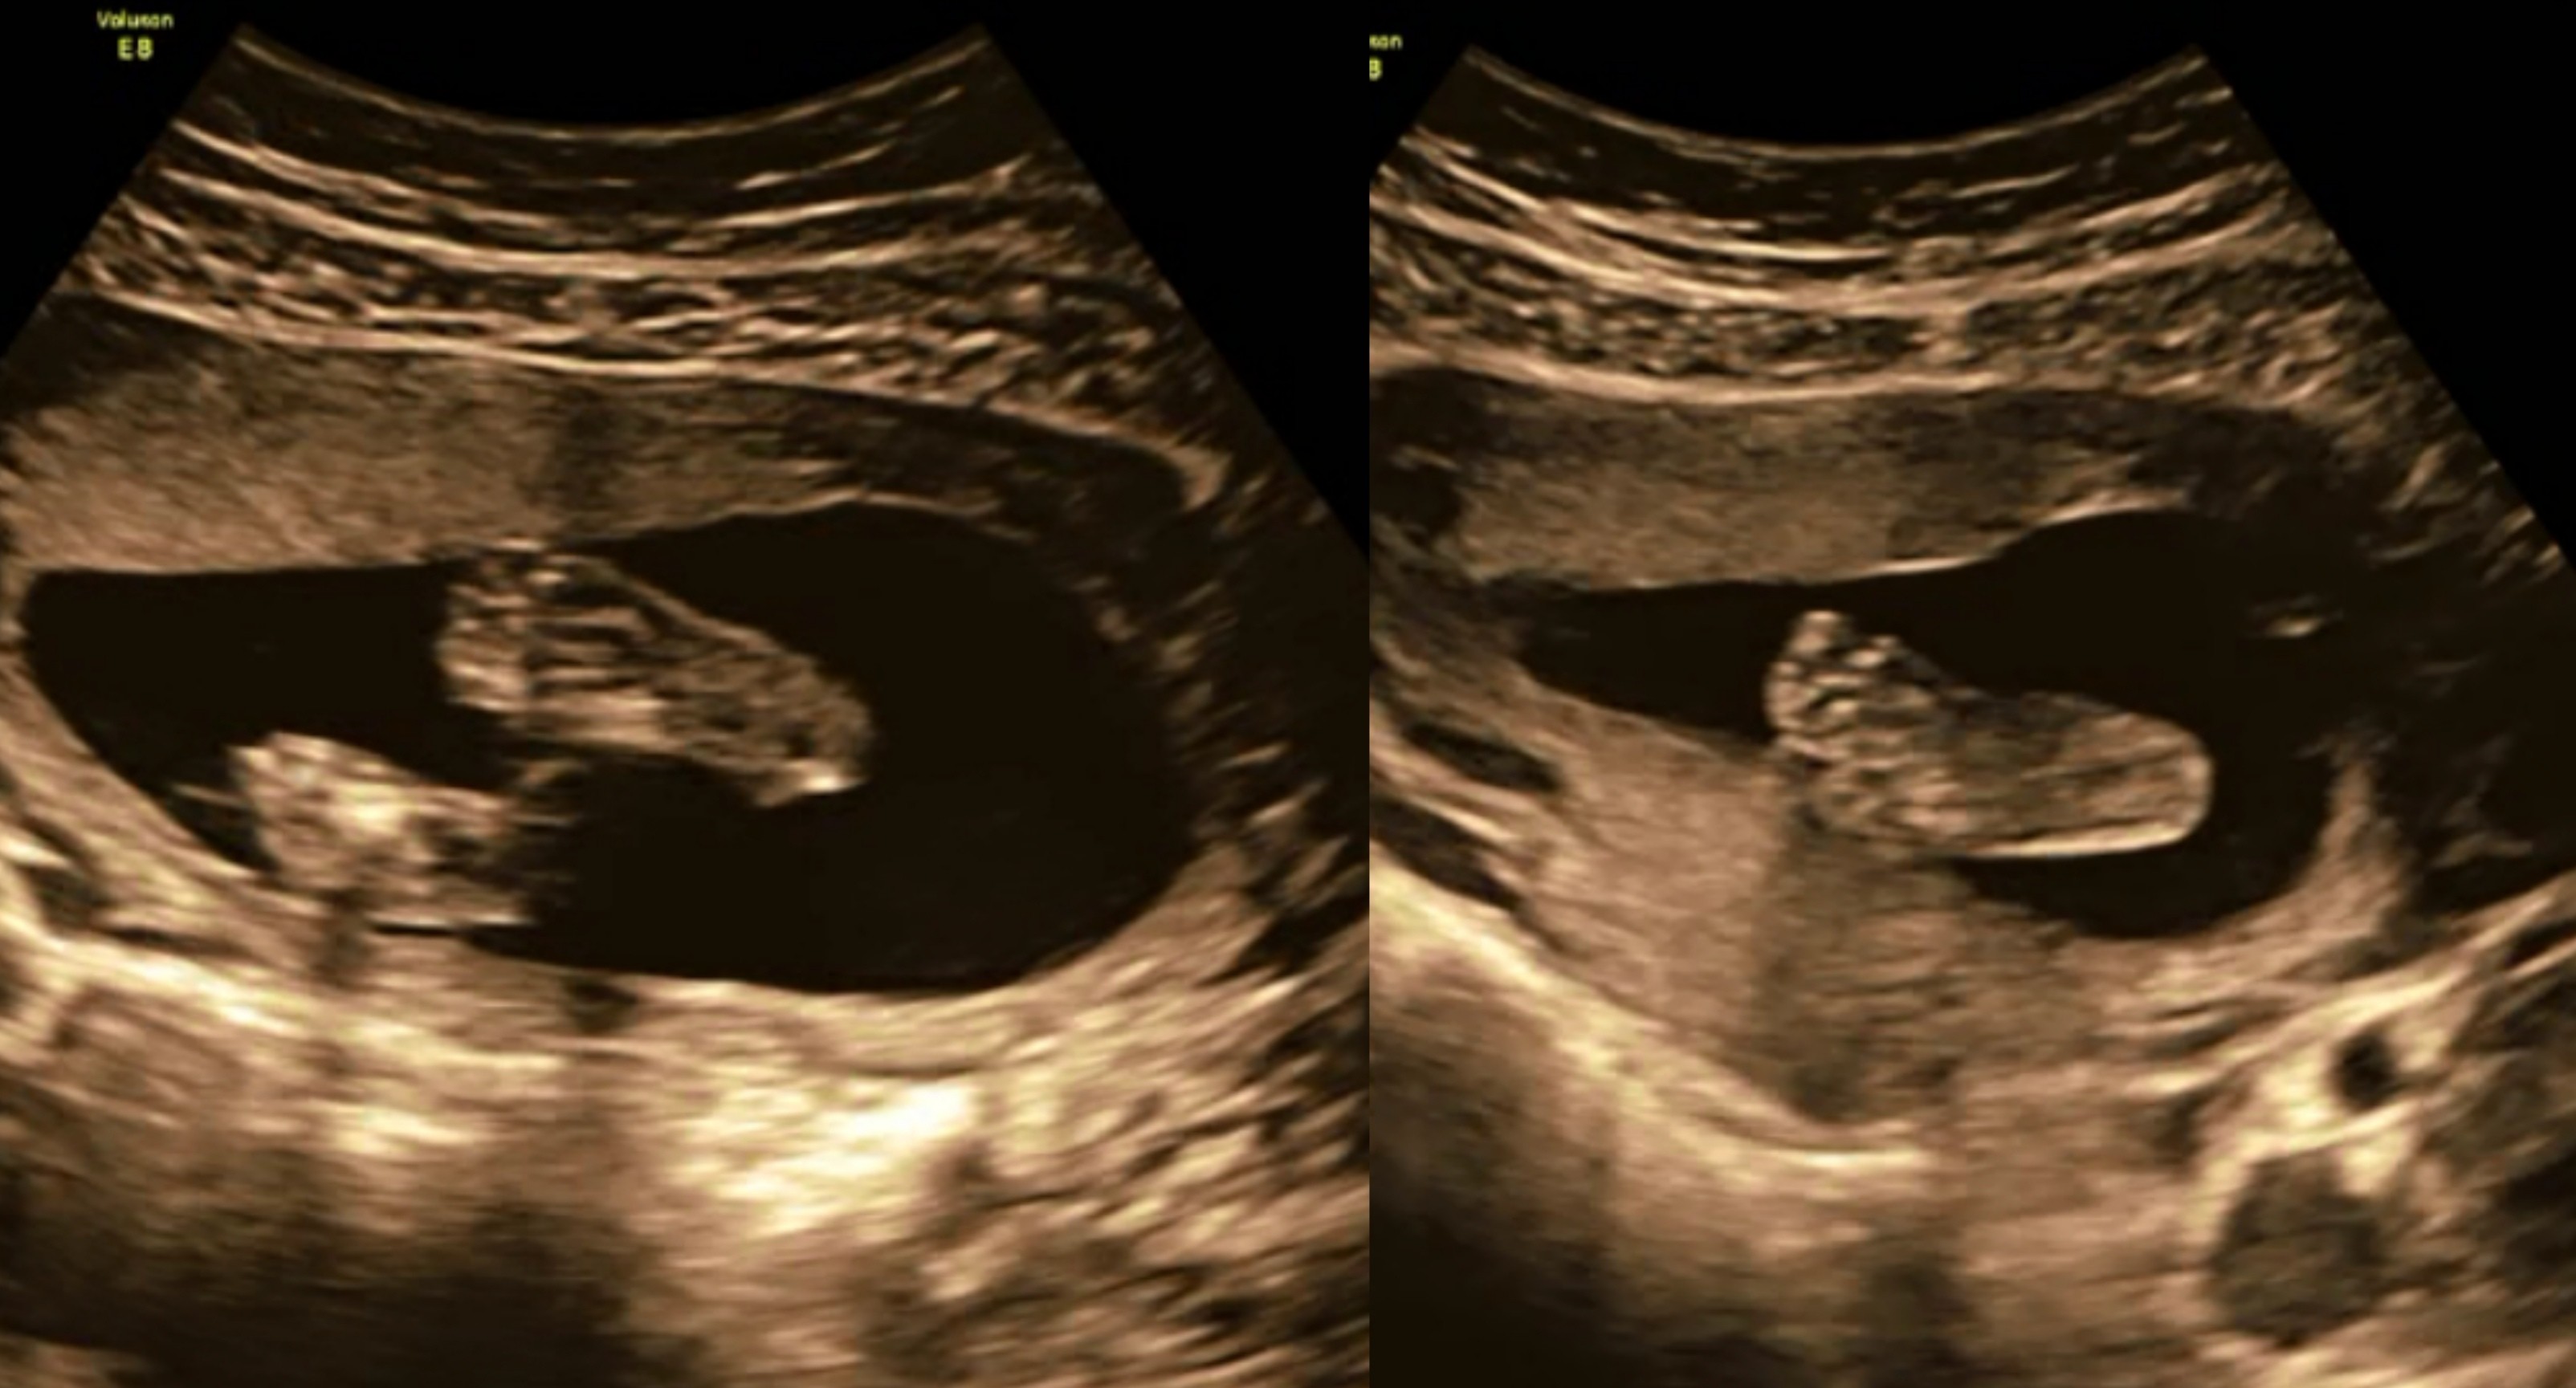

19+0 (wg usg i tego się teraz trzymamy!) wg OM 20+0

Waga : prawie 250 g i prawie 22 cm :biggrin2:

Tętno : 144(wczoraj), 150 (dzisiaj) :biggrin2:

Płeć : 100% chłopak :-) :)

Imię : Gabriel Mirosław :biggrin2:

Nosek - widoczny i śliczniutki (na prenatalnych podobno kośc nosowa była „nie do oceny”!)

Łożysko : na przedniej ścianie

Szyjka : 5 cm

Wszystkie narządy rozwijają się prawidłowo :-) :)

Termin porodu wg usg 20.04.2019 (jednak ze względu na cukrzycę typu2 nastąpi on 2 tygodnie wcześniej,ale konkretną datę poznam w późniejszym terminie) :-) :)